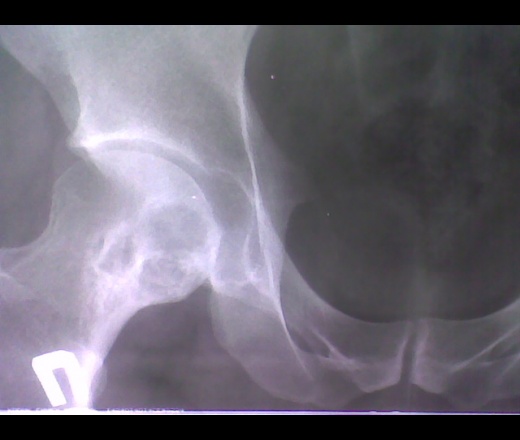

Пробегая с работы на работу, находясь на обеде - не caries sicca?

Чего-то, именно, на "сухую костоеду", не весьма похоже.

Я бы в первую очередь подумала о первично-хроническом остеомиелите.

А может какая фиброзная дисплазия? Сидит явно давно.В смысле "добро" какое то, ободок больно толстый. И странно, но слева суставная щель уже.

Экспансивного, тем более инфильтративного роста не видно. Что-то медленно раз"едает кость изнутри, причем успевает развиваться перифокальный склероз. А слева коксартроз.

Маловато склероза для остеомиелита с таким объемом деструкции.

Моё мнение.Фиброзная дисплазия-процесс врожденный,иногда склонный к прогрессированию,привел бы к раннему появлению жалоб(еще в детстве),деформации сегмента кости.Тут не видно,да и анамнез не подходящий.

Склеротический ободок(достаточно массивный) говорит о предшествующей резорбции,если нет инфекционного анамнеза,то скорее всего-это ДОА с кистозной перестройкой справа III ст., ДОА слева - II ст.

Более всего похоже на хронический остеомиелит...

Что-то не покидает мысль о ТБС...Надо бы заглянуть в Рейнберга.

Cегодня разговаривал с пациентом сам: жалоб со стороны тазобедренных суставов у него нет и вобщем-то и не было, как и травм. Со стороны кистей и стоп беспокоят скорее не боли а парестезии по типу "ползания мурашек", ранее предполагалось, что это возможно связано с болезнью Рейно( со слов пациента).

Очень похоже на Педжета ... и эозинофильные гранулемы. Но, это у меня погрешность в изображении или справа в межвертельной зоне, слева - в шейке и дистальнее участки деструкции без склерозированных контуров? Если таковые есть на самом деле, можно думать об MTS (не исключаются 2 самостоятельных процесса).

Есть мнение, и не только моё, что это веллонодулярный синовiт.

Vlasov писал: "Есть мнение, и не только моё, что это веллонодулярный синовiт."

Коллега, спасибо за отзыв по демонстрации. Если честно, то даже не слышал о патологии названной вами. Прошло почти 2 года, с того момента как случай представлялся, если смогу что-то узнать, в плане верификации, сообщу.

http://www.radiomed.ru/publications/kss-sinovit-pigmentnyi-villezonodulyarnyi

Cпасибо, за полезную ссылку. В голове крутится, что подобные картинки попадались, но не знал, что они могут иметь отношение к указанной патологии.